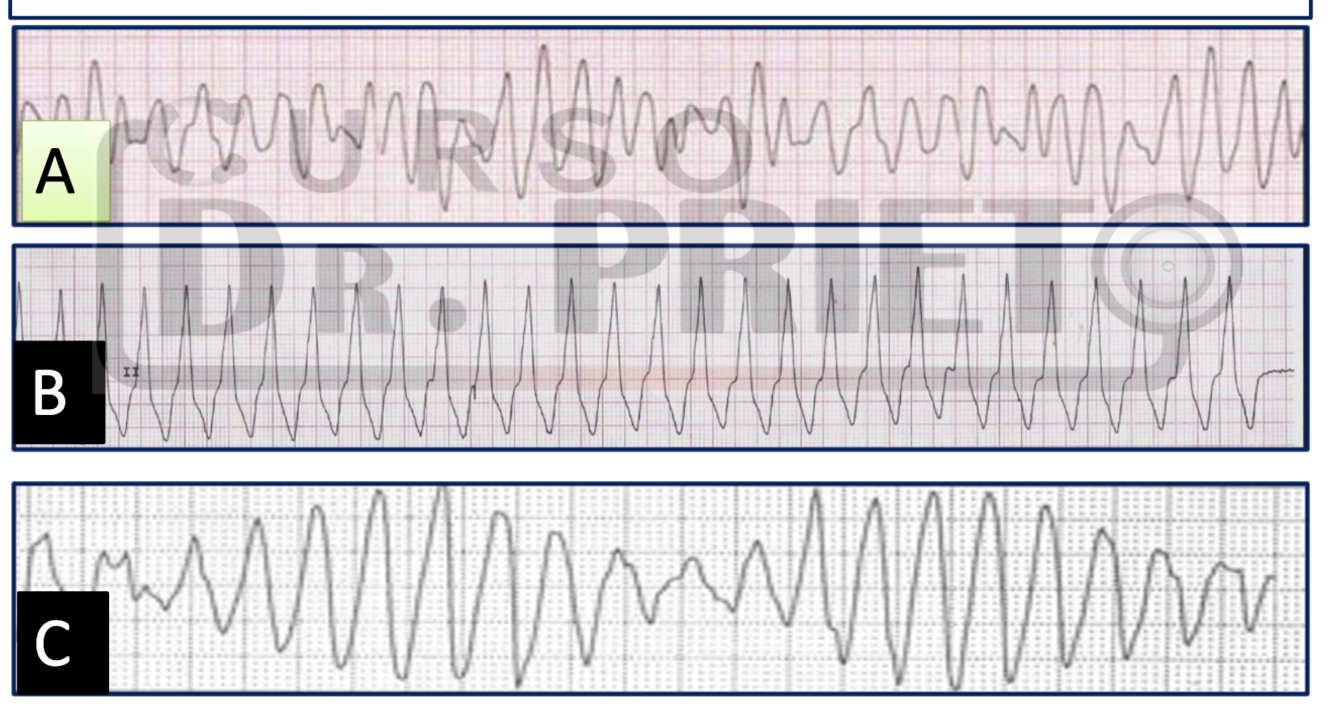

ELECTRO IMAGENES 2.

• A: Fibrilacion ventricular.

• B: Taquicardia ventricular monomorfica.

• C: Taquicardia ventricular polimorfa del tipo puntas torcidas.